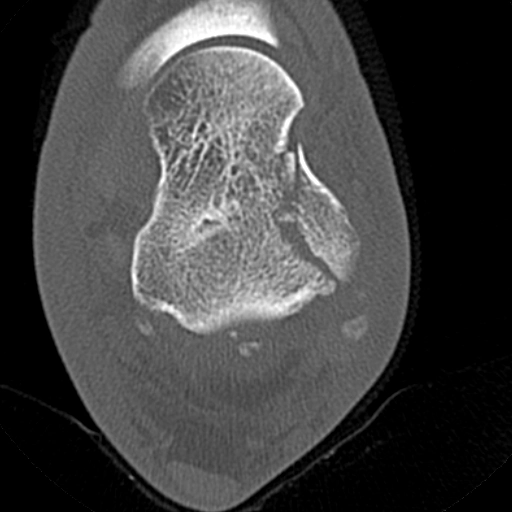

Gãy xương gót (Calcaneal fracture)